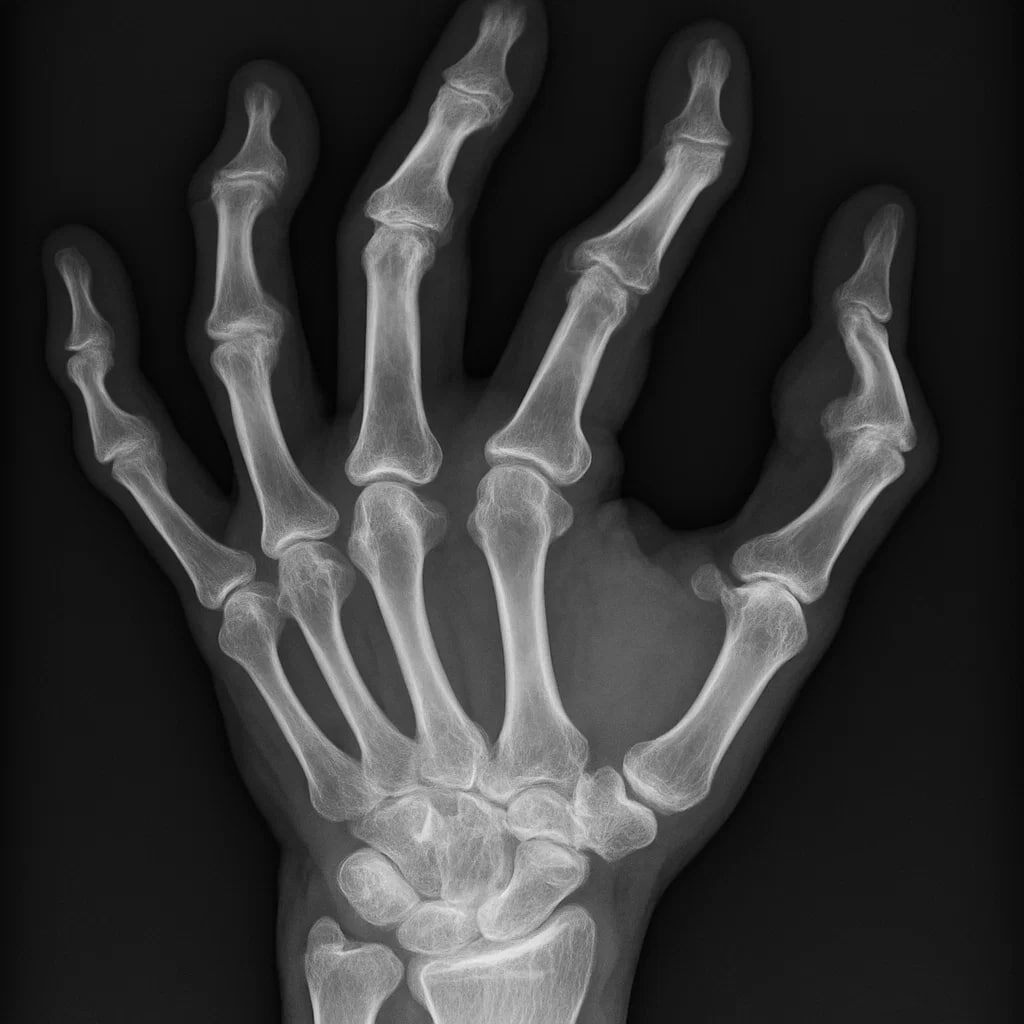

Ревматоидный артрит — это не просто “боль в суставах”.

Это форма хронического воспаления, при котором иммунная система теряет контроль и начинает разрушать собственные ткани.

Иммунные клетки воспринимают суставную оболочку как чужеродную.

Начинается воспаление, сустав отекает, болит, деформируется.

Со временем процесс перестаёт быть локальным — воспаление становится системным, затрагивая сосуды, лёгкие, сердце.

⏺утренняя скованность — пальцы “не слушаются”

⏺боль и припухлость в мелких суставах кистей, стоп